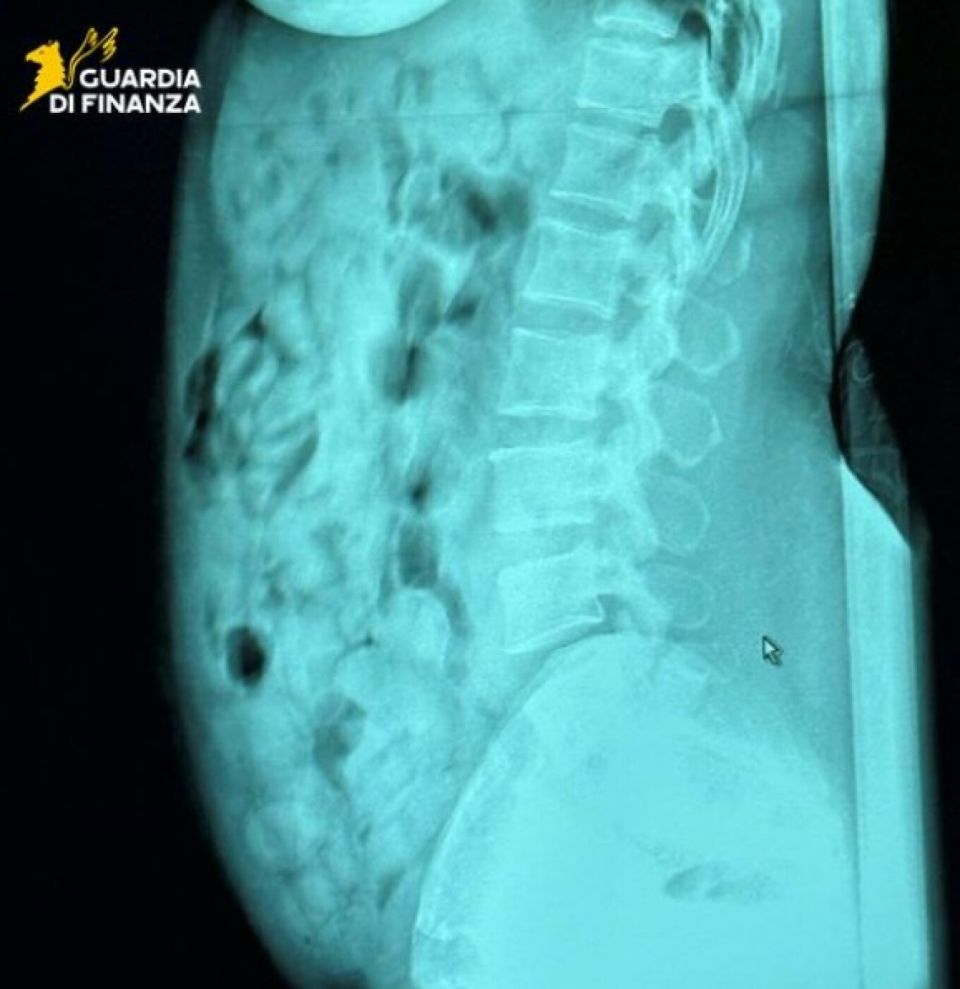

Ακτινολογικές εξετάσεις που πραγματοποιήθηκαν στο νοσοκομείο του Μπέργκαμο επιβεβαίωσαν ότι η γυναίκα είχε καταπιεί 120 σφαιρίδια, σχεδόν 1.393 γραμμαρίων ηρωίνης και τα οποία ήταν σφραγισμένα με κολλητική ταινία με προορισμό τη Σαρδηνία.